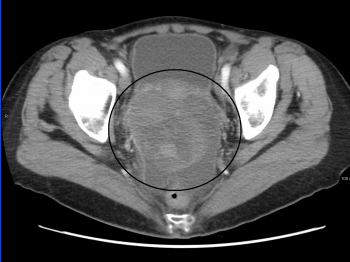

При раке яичников грамотная, точная диагностика имеет крайне большое значение, так как именно ее результаты определяют тактику дальнейшего лечения и его успешность, а у женщин молодого возраста и возможность сохранения репродуктивной функции. В настоящее время наиболее распространенным ранним методом выявления рака яичника является исследование крови на онкомаркеры СА 125 и НЕ 4. При подозрении на рак назначается подробное обследование, включающее КТ, МРТ, ПЭТ-КТ. При раке яичников иногда бывает сложно точно определить стадию, в этом случае прибегают к диагностической лапароскопии, которая в случае необходимости может быть сразу переведена в лечебную. Важно и то, что цены на лечение рака яичников за рубежом зависят от объема лечения, поэтому, чем раньше диагностировано заболевание, тем меньший объем лечебных процедур потребуется, и тем меньше оно будет стоить.